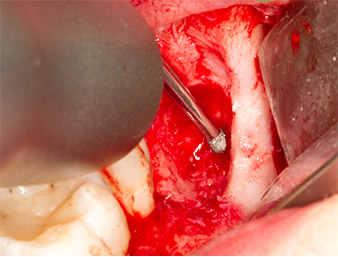

After block and local anaesthesia, the operating site was opened up and the soft tissue exposed for buccal retromolar access (Fig. 3).

sulcular incision

Fig. 3: The sulcular incision begins in mid-tooth 36 (LL6), with distal extension on the ascending ramus.

The tissue above the root remnant was not completely ossified and consisted for the most part of granulation tissue modified by inflammation (Fig. 4).

Granulation tissue

Fig. 4: Two Langenbeck retractors and a raspatorium expose the operating area. Granulation tissue of the incompletely healed first osteotomy can be seen.